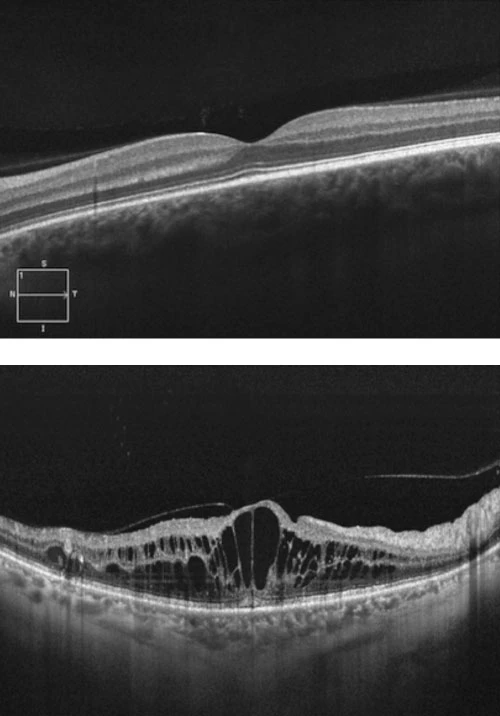

Branch retinal vein occlusion results in venous stasis, and if significant, can cause secondary retinal ischaemia. This can in turn result in neovascular complications such as glaucoma, vitreous haemorrhage and retinal traction. In addition, BRVO is often associated with macular oedema, which causes vision loss. The presence and extent of macular oedema can be measures by an ocular coherence tomogram (OCT), which is a useful tool for documenting the response to treatment.

Ocular Coherence Tomogram (OCT)

Prior to the advent of intravitreal anti-VEGF agents, retinal photocoagulation (laser) was the mainstay of treatment of BRVO with underwhelming results for recovery of vision. Ranibizumab (Lucentis™) which is an anti-vascular endothelial growth factor A (VEGF-A) monoclonal antibody fragment has largely superseded laser for management of macular oedema due to BRVO. Lucentis™ is delivered into the eye by intravitreal injection, with most patients requiring a course of treatment, which begins monthly, and is subsequently extended according to response. Response to treatment is measured by improvement of vision and resolution of macular oedema on OCT.